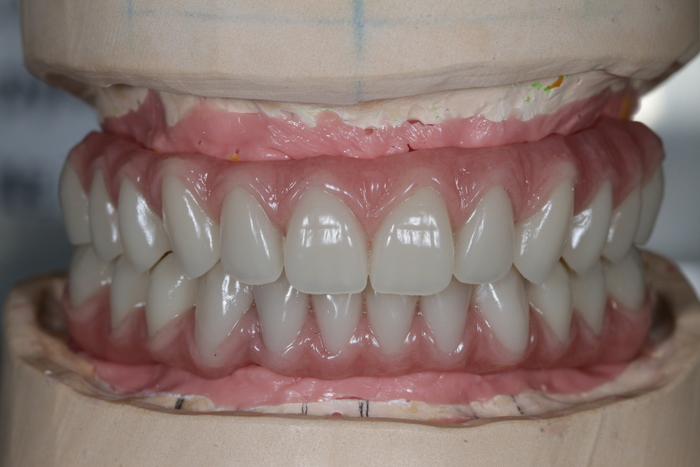

Далее ортопедом были сняты слепки, а техник в лаборатории изготовил вот такой постоянный протез с опорой на имплантатах.

И, наконец, вот так выглядит протез в полости рта